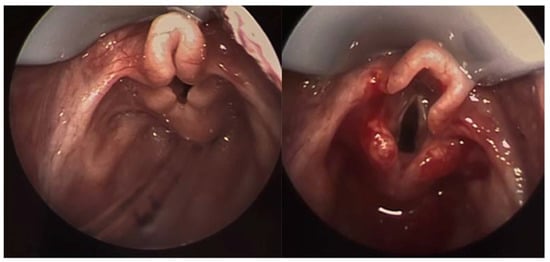

2.1. Laryngomalacia